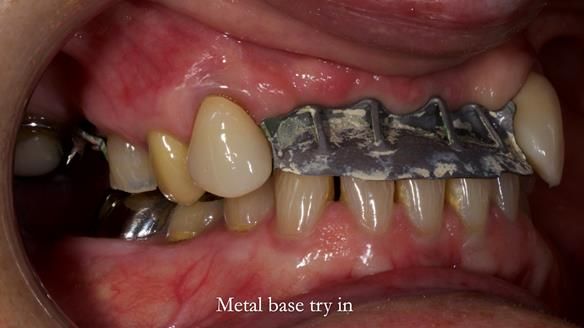

- Metalwork framework try-in – to verify fit, path of insertion, and support.